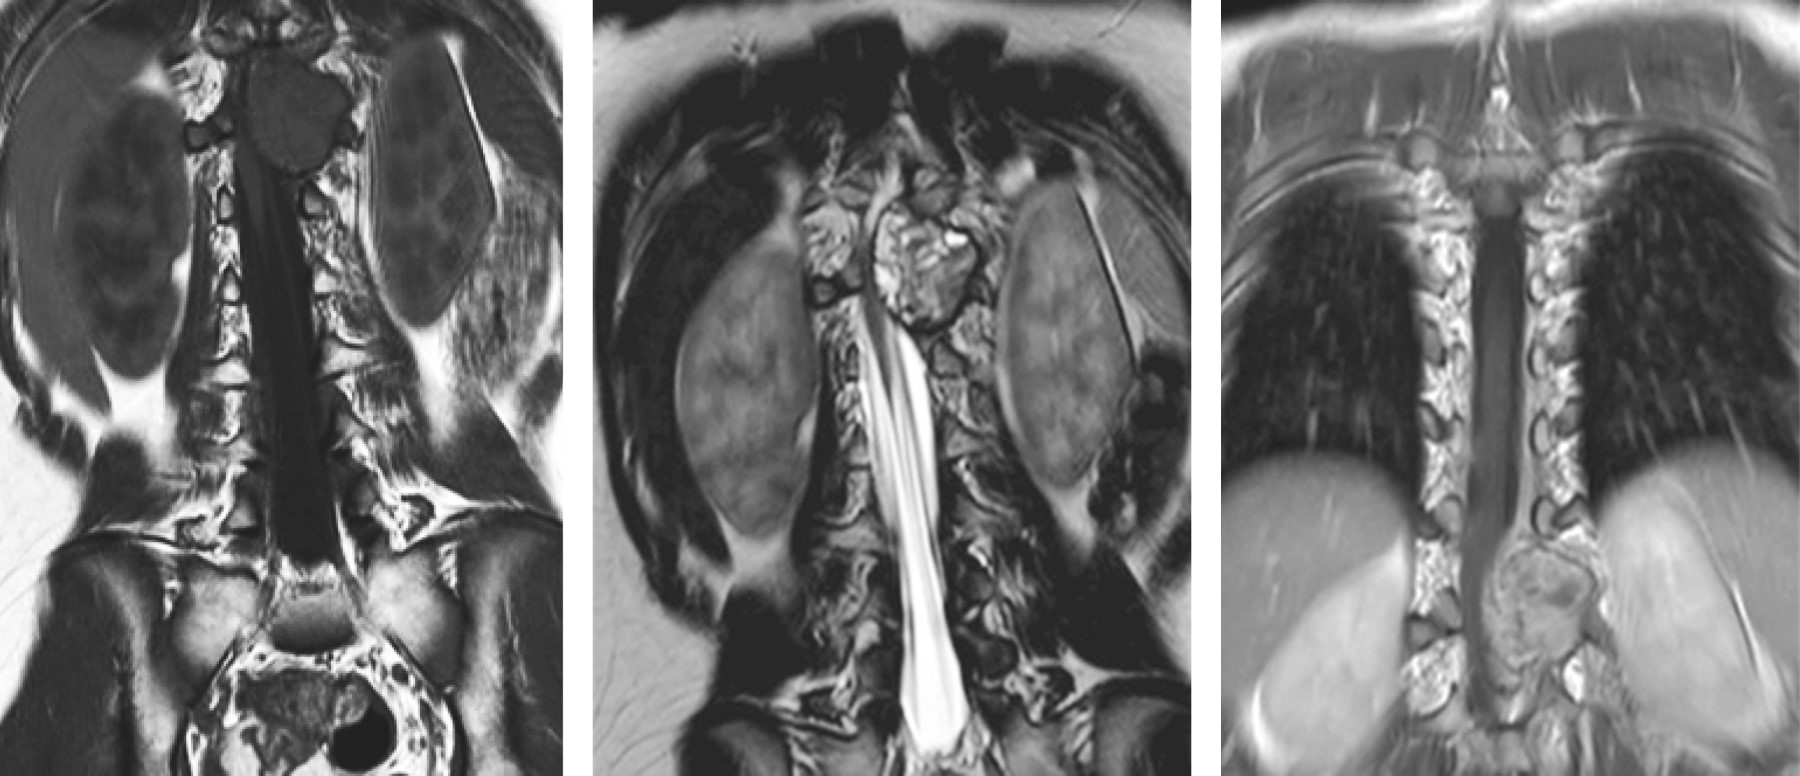

La RM simple y contrastada caracterizó de mejor forma lesión, siendo extradural, heterogénea, con una porción multilocular con niveles líquido-líquido observados hiperintensos en T2; presentaba también una porción sólida que realzaba al contraste, la cual invadía al canal medular generando invasión anteriormente hacia el cuerpo vertebral, con destrucción del pedículo, proceso transverso y la lámina (Figuras 2, 3, 4, 5 y 6).